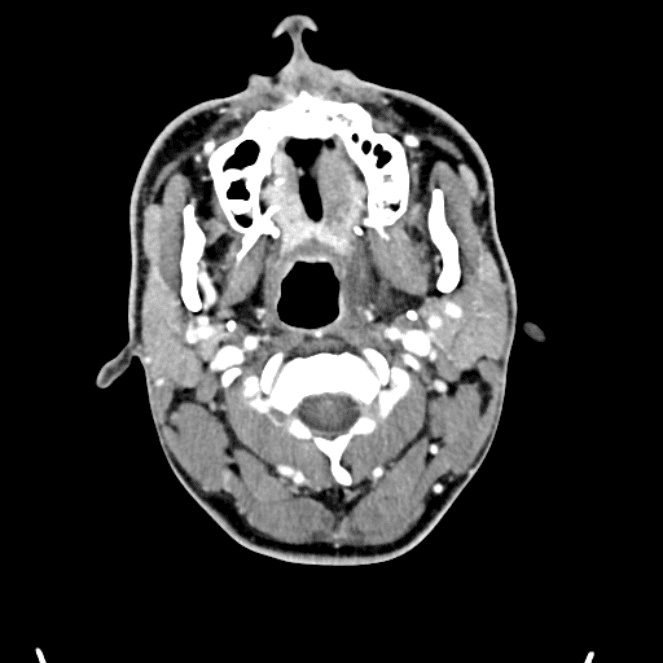

Head and Neck

Practice

Simulates call by including subtle or difficult cases and some normals.

27 cases